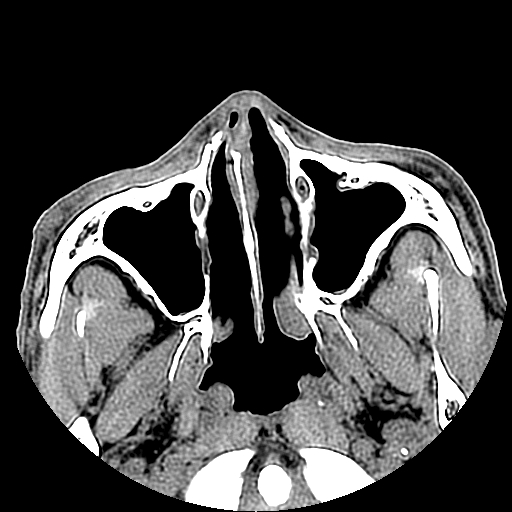

以下是引用liaoqiang在2008-7-16 21:15:00的发言:[br]右侧鼻骨骨折

以下是引用zxd95在2008-7-16 21:39:00的发言:[br]右侧上颌骨额突骨折。[br][br][br][br]